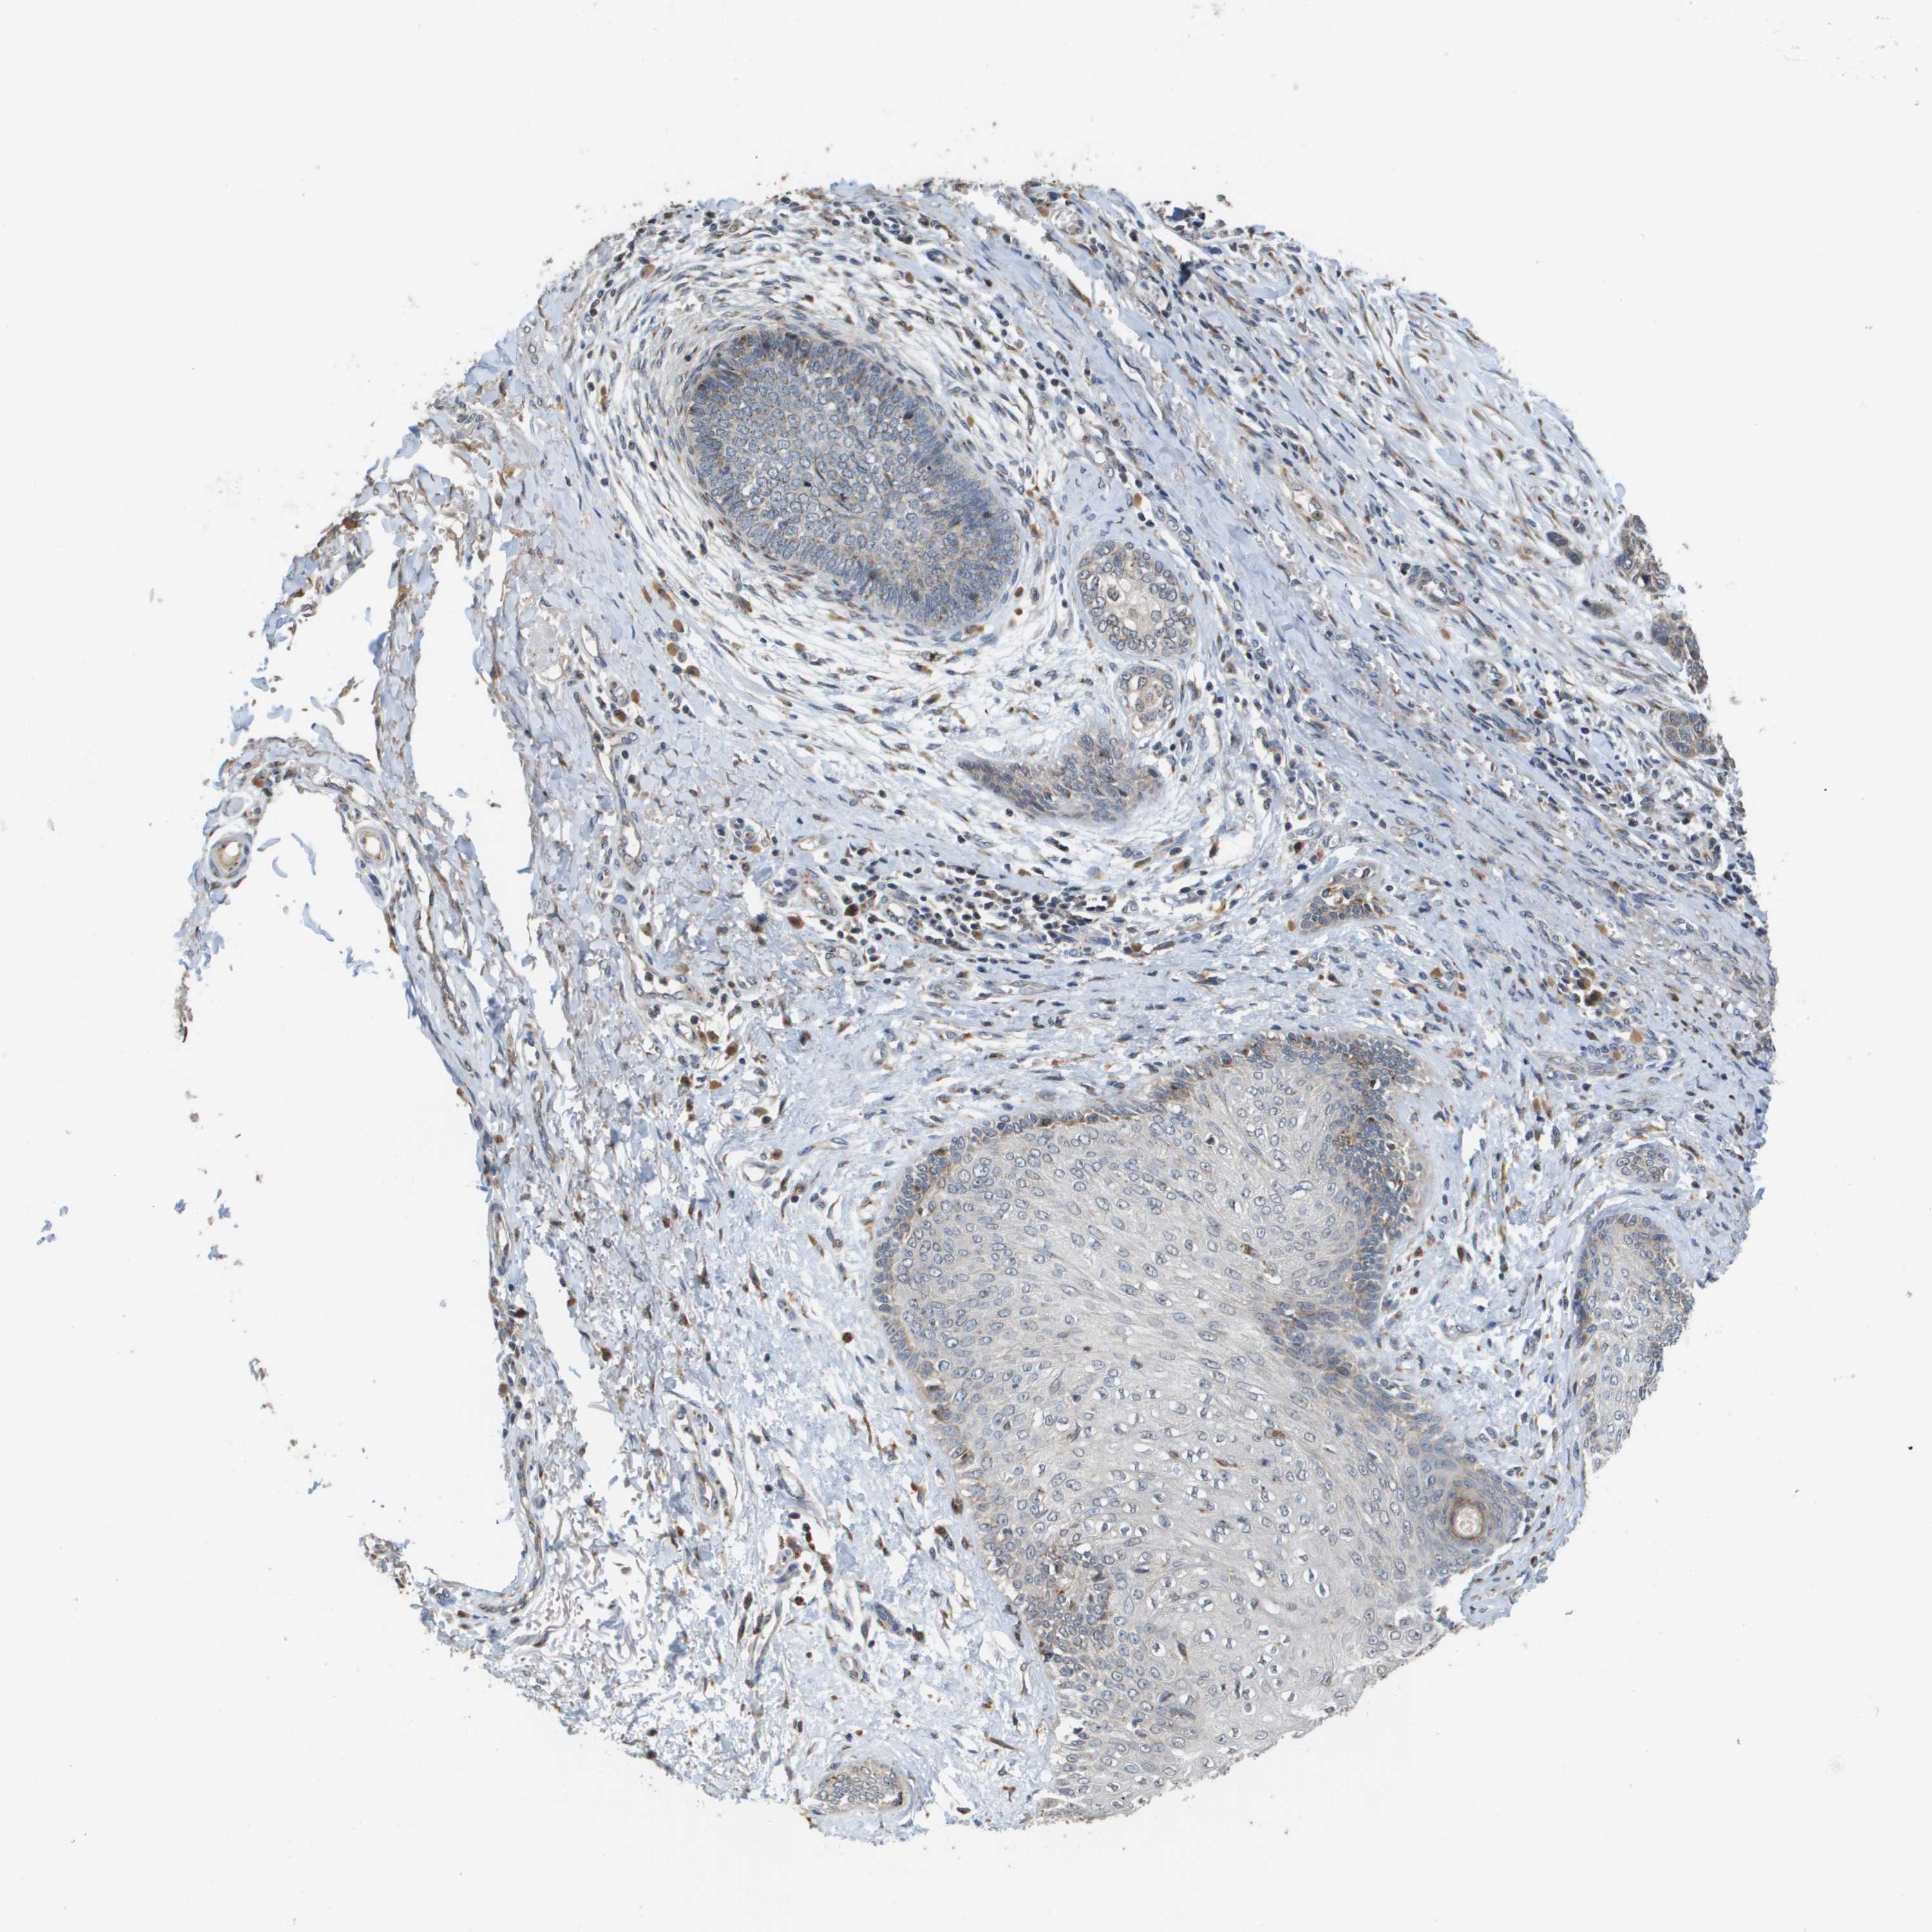

SKIN CANCER - Protein expressioni

A mouse-over function shows sample information and annotation data. Click on an image to view it in a full screen mode. Samples can be filtered based on level of antibody staining by selecting one or several of the following categories: high, medium, low and not detected. The assay and annotation is described here.

Each image is clickable and will lead to virtual microscopy that enables deeper exploration of all samples and also displays staining intensity scores, fraction scores and subcellular localization as well as patient and tissue information for each sample.

Antibody HPA006277

Antibody HPA006507

Antibody CAB017027

Staining

High

Medium

Low

Not detected

Intensity

Strong

Moderate

Weak

Negative

Quantity

>75%

75%-25%

<25%

None

Location

Nuclear

Cytoplasmic/membranous

Cytoplasmic/membranous,nuclear

Squamous cell carcinoma, NOS